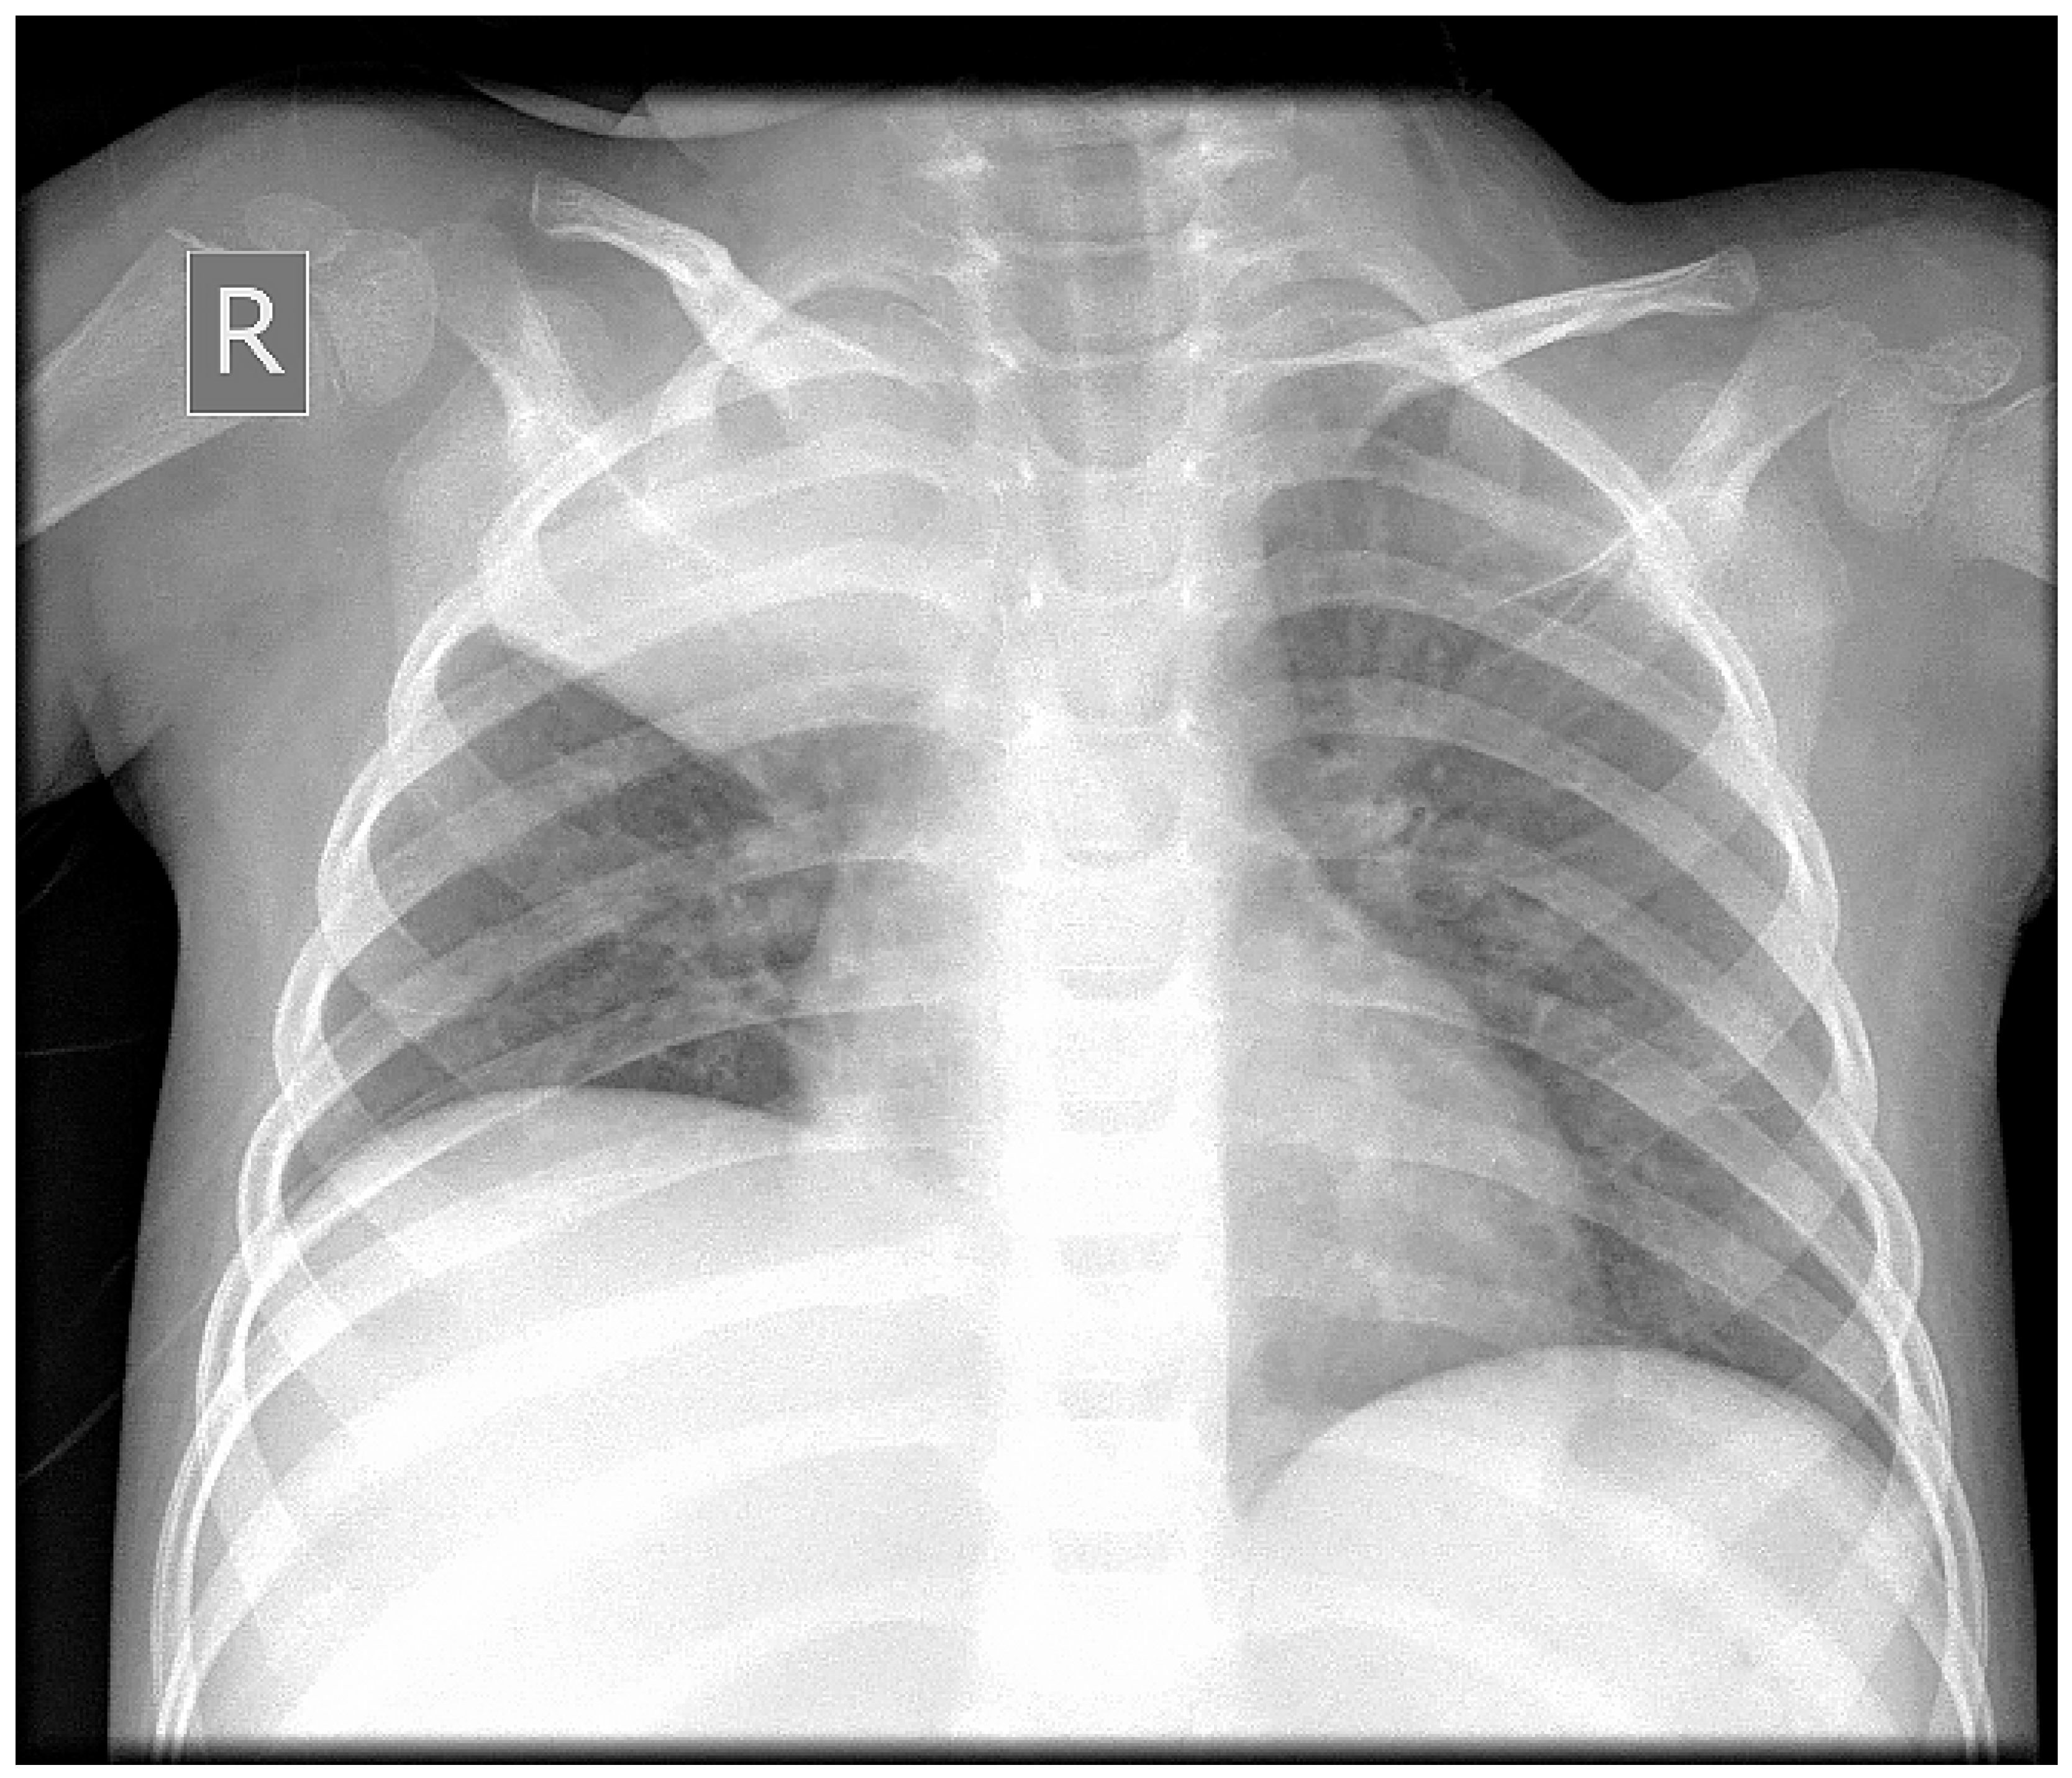

2. Case Report